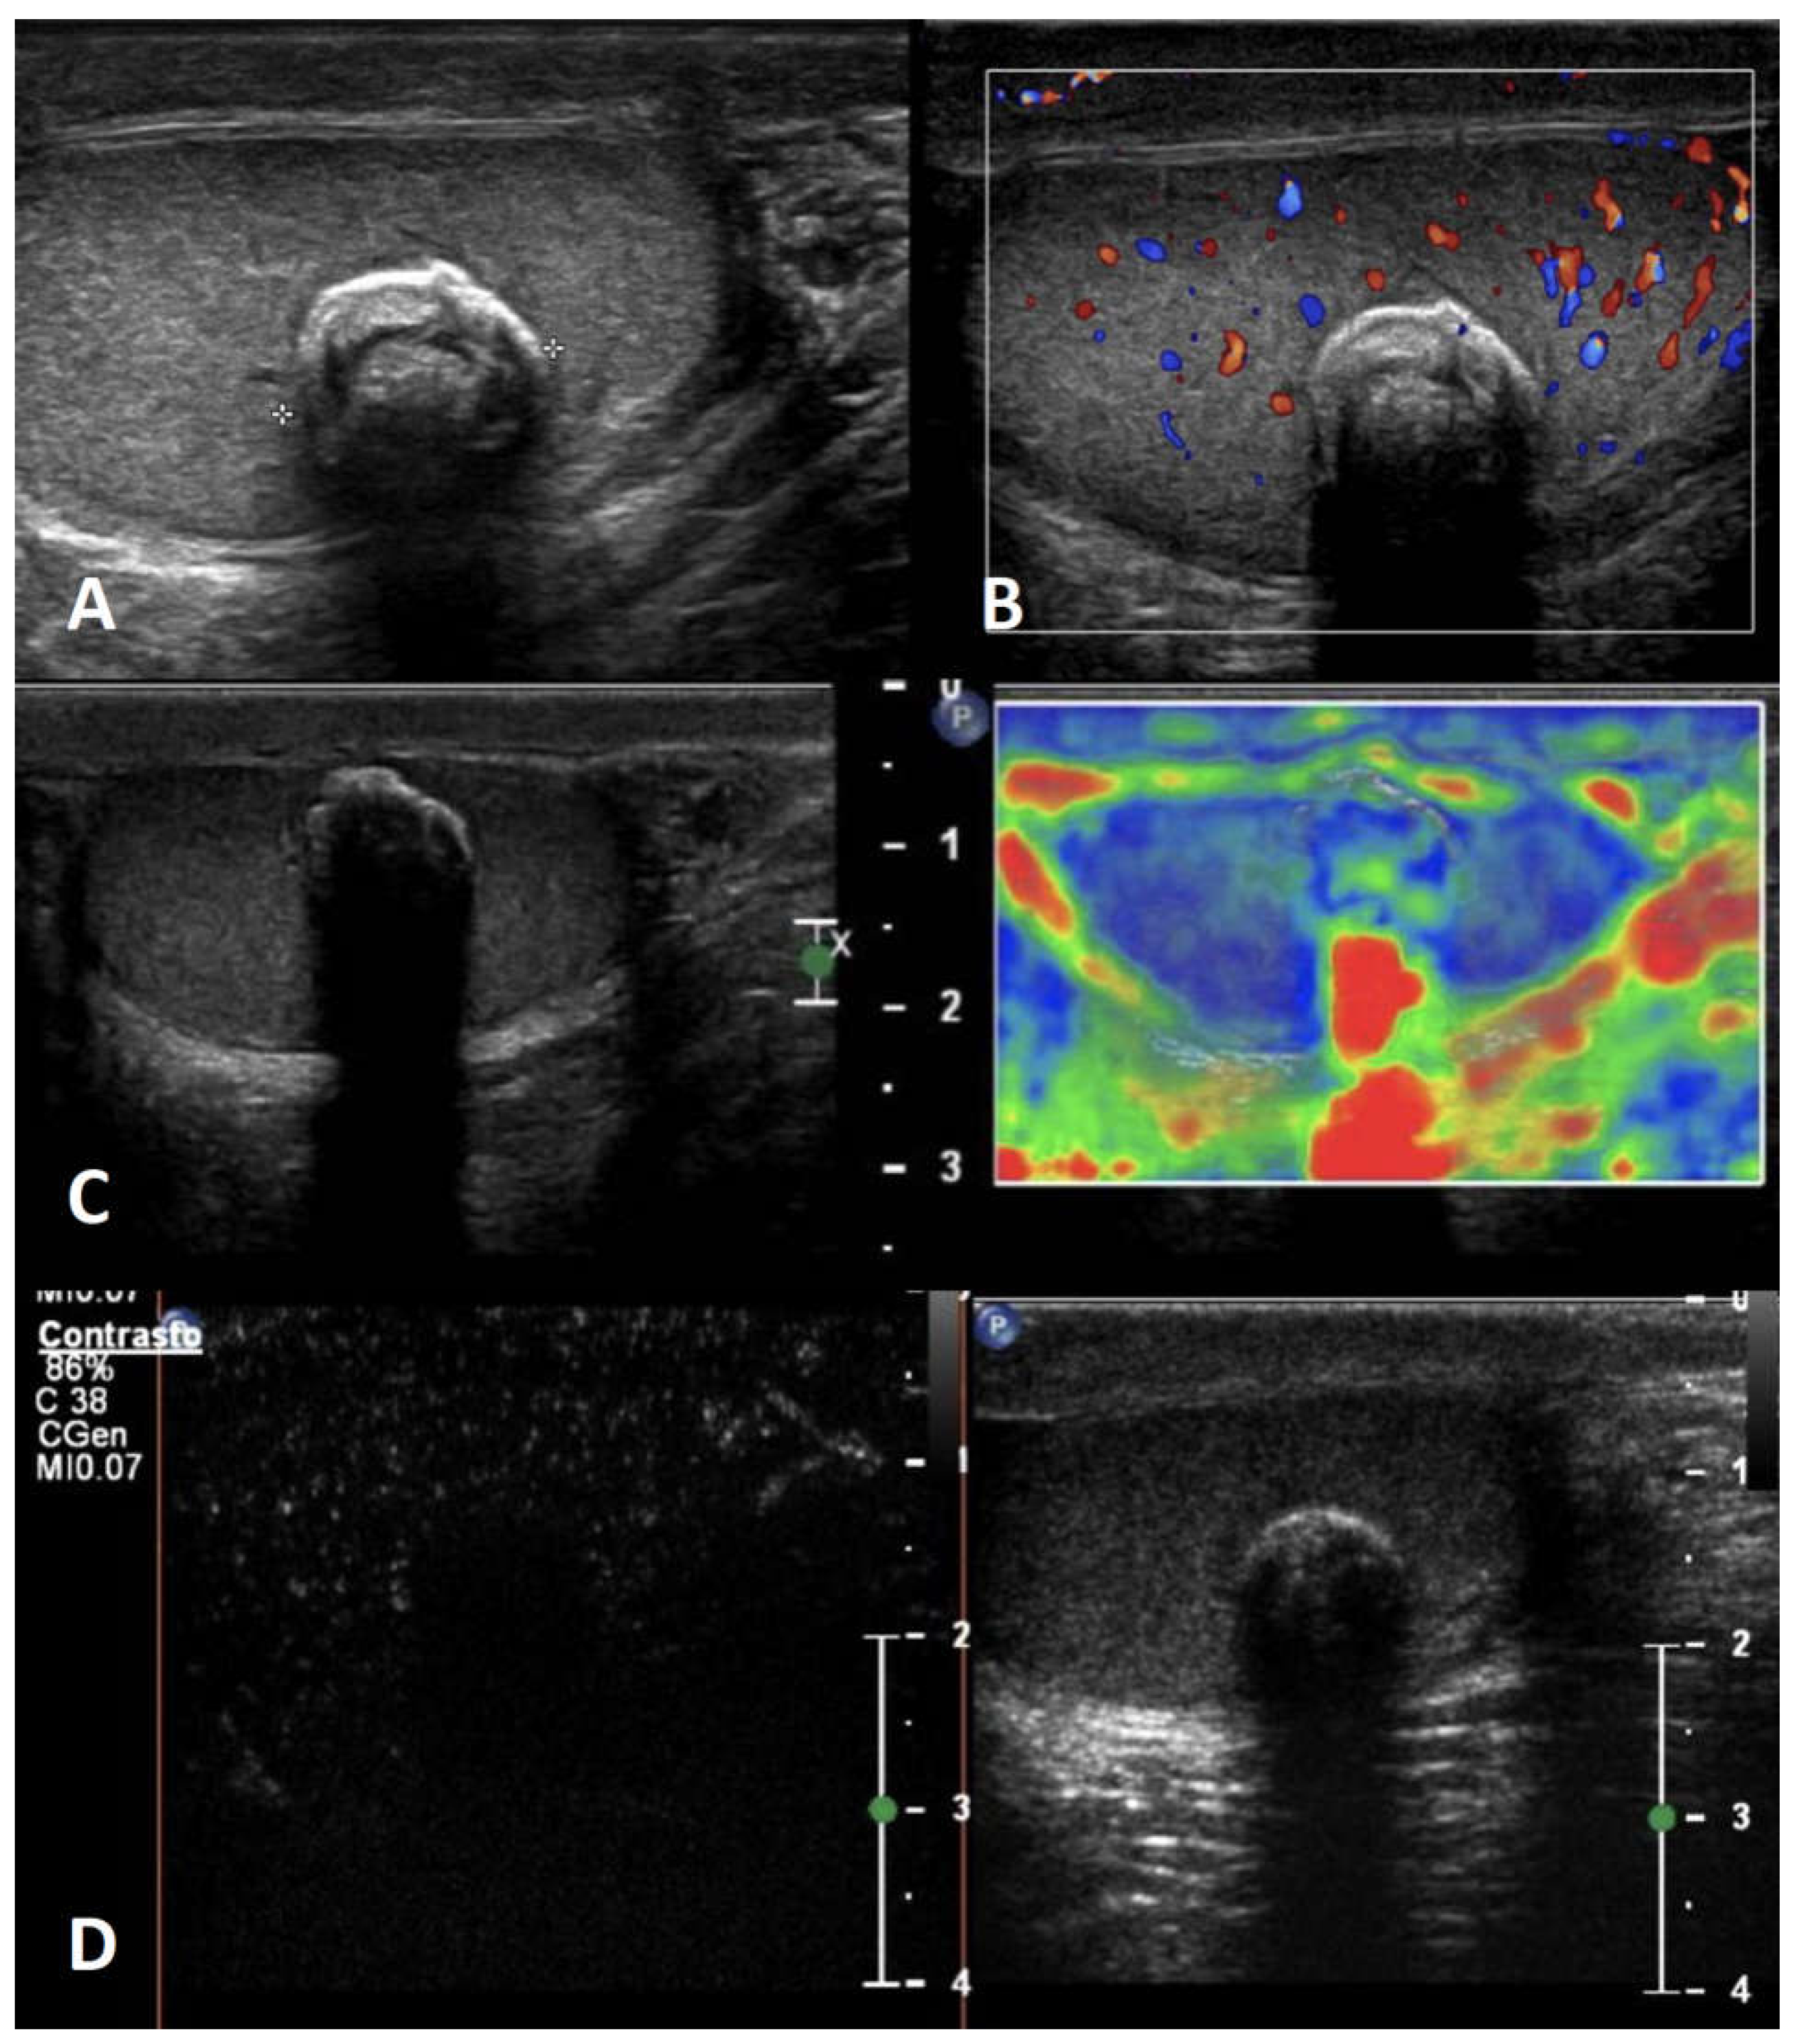

5.2. Epidermoid cysts

| Non-neoplastic intratesticular lesions | |||||

|---|---|---|---|---|---|

| Clinical presentation | GSUS | CDUS | CEUS | SE | |

| Simple cyst | asymptomatic/ incidental finding, usually not palpable |

rounded anechoic lesions with thin, clear, hyperechoic wall and posterior acoustic enhancement | avascular | unenhanced | soft lesion with high elastic strain |

| Epidermoid cyst | asymptomatic/ can be palpable |

well circumscribed rounded lesion with “onion ring” aspect (concentric hypo- and hyper-echoic rings) OR densely calcified mass with acoustic shadow OR cyst with hypoechoic rim and central calcification OR mixed atypical pattern | avascular | unenhanced/ perilesional rim enhancement |

hard lesion with low/absent elastic strain |

| Adrenal rest | patients with CAH; usually not palpable |

hypoechoic lesions with irregular margins, hyperechogenic foci, typically localized in the mediastinum testis, usually bilateral | markedly vascularized |

hyperenhanced | hard lesions with low/absent elastic strain |